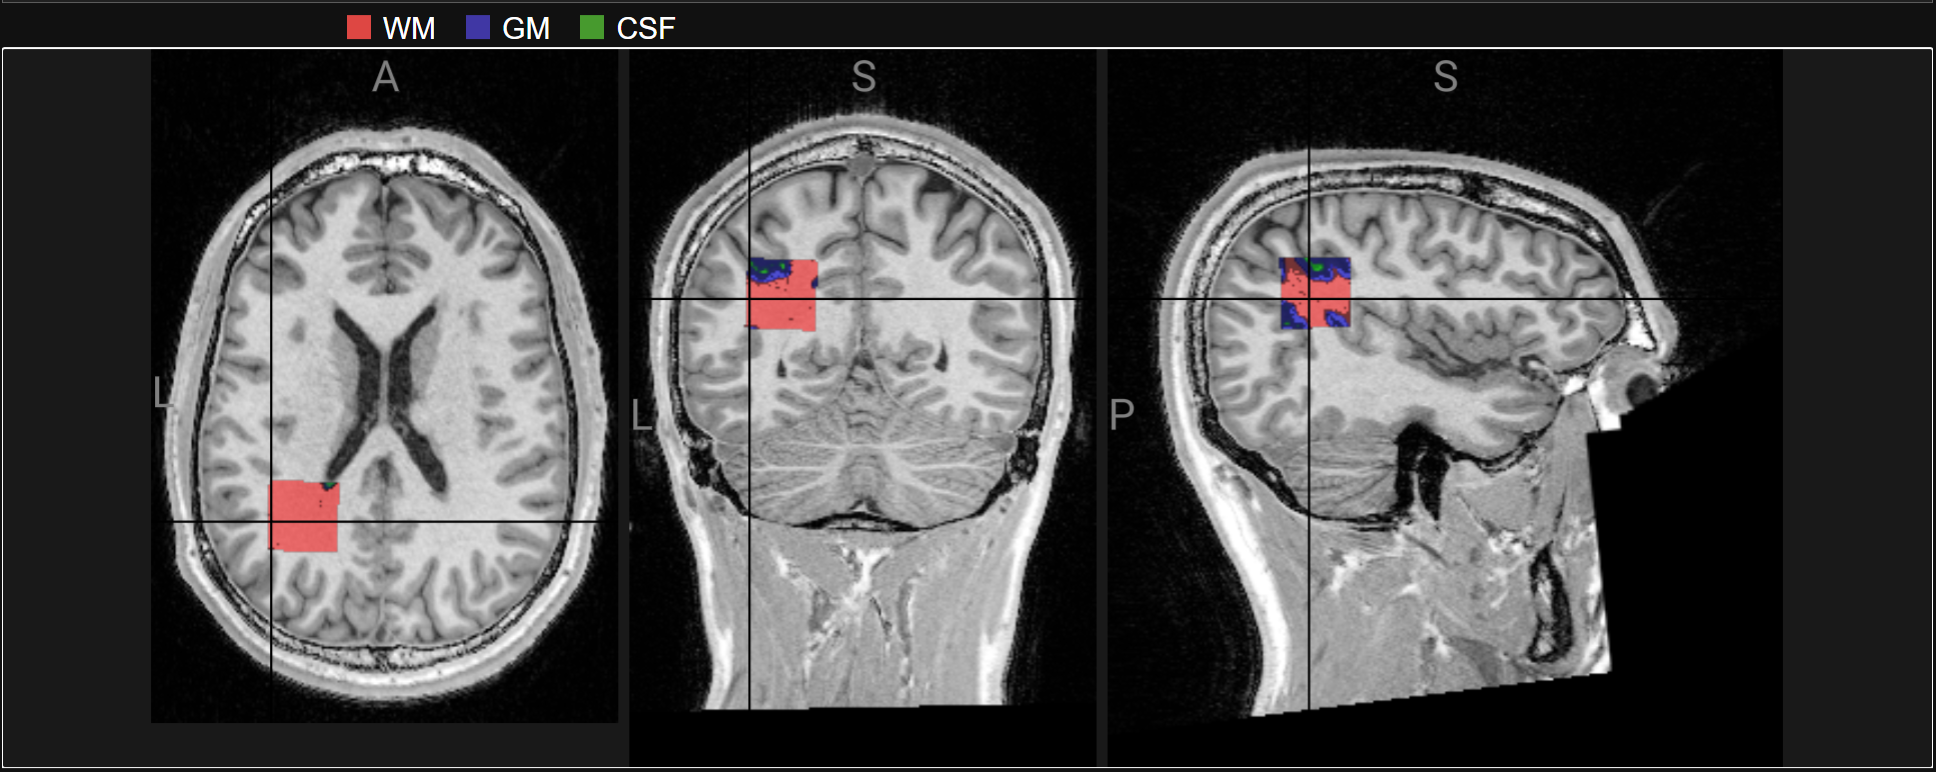

Osprey performs alignment with T1

Osprey also performs segmentation to determine the proportion of tissue types within the voxel (for WM and CSF correction)

display(panel)

display(ipython_image(url='https://raw.githubusercontent.com/neurodesk/example-notebooks/refs/heads/main/books/images/osprey-notebook.png'))